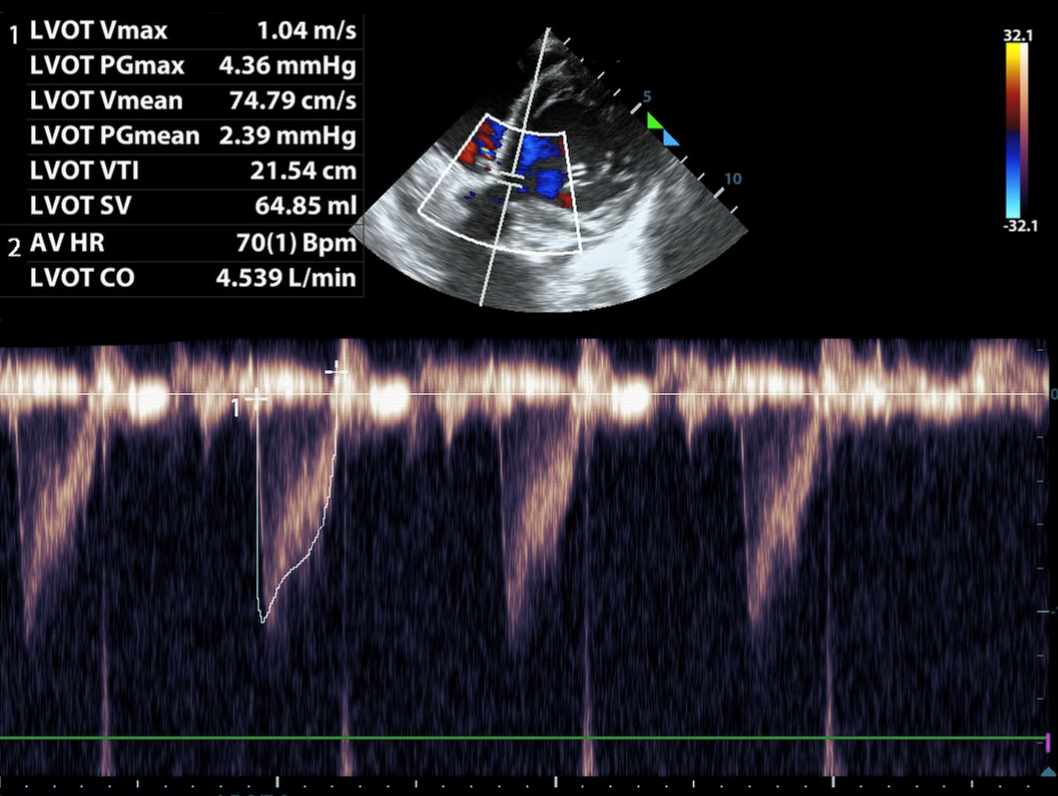

TEE Resus VTI - With Measurement Image